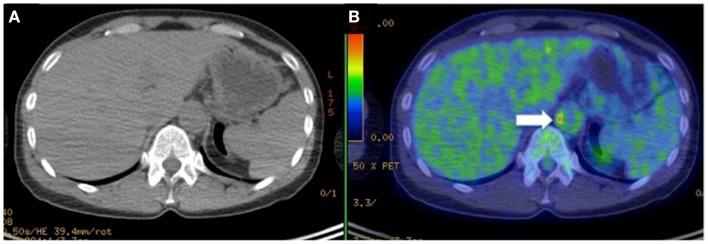

In large-vessel vasculitides, inflammatory infiltrates may cause thickening of the involved arterial vessel wall leading to progressive stenosis and occlusion. Dilatation, aneurysm formation, and thrombosis may also ensue. Activated macrophages and T lymphocytes are fundamental elements in vascular inflammation. The amount and density of the inflammatory infiltrate is directly linked to local disease activity. Additionally, patients with autoimmune disorders have an increased cardiovascular (CV) risk compared with age-matched healthy individuals as a consequence of accelerated atherosclerosis. Molecular imaging techniques targeting activated macrophages, neovascularization, or increased cellular metabolic activity can represent effective means of non-invasive detection of vascular inflammation. In the present review, novel non-invasive imaging tools that have been successfully tested in humans will be presented. These include contrast-enhanced ultrasonography, which allows detection of neovessels within the wall of inflamed arteries; contrast-enhanced CV magnetic resonance that can detect increased thickness of the arterial wall, usually associated with edema, or mural enhancement using T2 and post-contrast T1-weighted sequences, respectively; and positron emission tomography associated with radio-tracers such as [(18)F]-fluorodeoxyglucose and the new [(11)C]-PK11195 in combination with computed tomography angiography to detect activated macrophages within the vessel wall. Imaging techniques are useful in the diagnostic work-up of large- and medium-vessel vasculitides, to monitor disease activity and the response to treatments. Finally, molecular imaging targets can provide new clues about the pathogenesis and evolution of immune-mediated disorders involving arterial vessels.